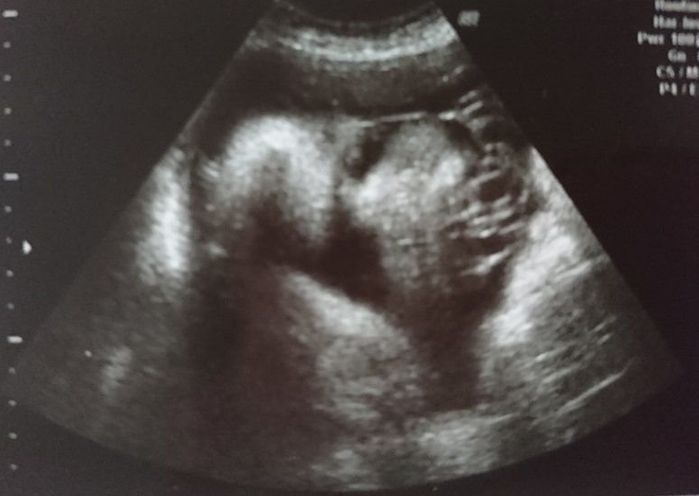

妊娠27週目のエコー写真 おなかがますます大きくなりました

おなかはもうすぐ100cmに達しそうです。おなかが大きすぎて腰痛が悪化し、立っているのがつらくなりました。赤ちゃんにまつ毛やまゆ毛が生えてくる時期だそうです。エコー写真は大仏様のような穏やかな顔に見え、3D画像は外人さんのように鼻が高く見えたので、どんなイケメンなのか、息子に会うのがとても楽しみになりました。赤ちゃんの推定体重は1324gでした。